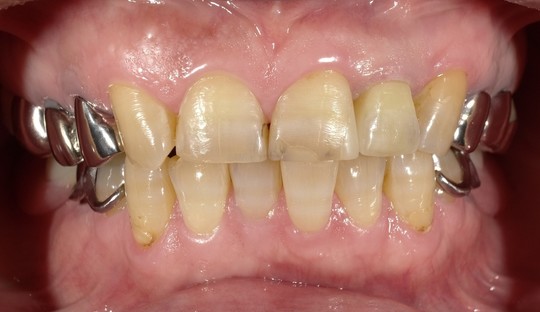

e.max クラウン

BEFORE

AFTER

年齢:50代女性

治療内容:左上真ん中から2番目の歯で、他院様での修復物不適合で見た目を気にされてご相談を受けました。e.maxクラウンの審美修復で、ご自身の歯に近い自然で美しい見た目に仕上がりました。

治療期間/通院回数:3回

費用: e.max クラウン 110,000円 ※2025年7月現在の価格